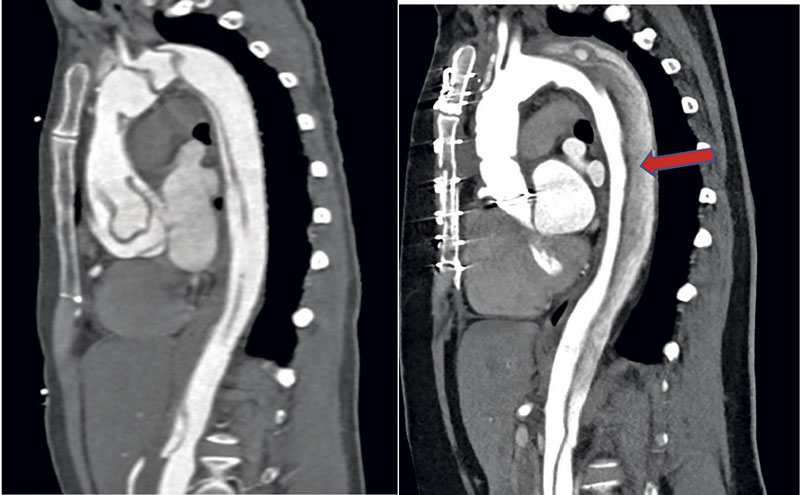

Till vänster: Akut typ A-dissektion med engagemang av ascendens, arcus och descendens. Till höger: Samma patient 1 år senare, efter åtgärd med inopererat mekaniskt kompositgraft. Röd pil visar trombotiserat falskt lumen.